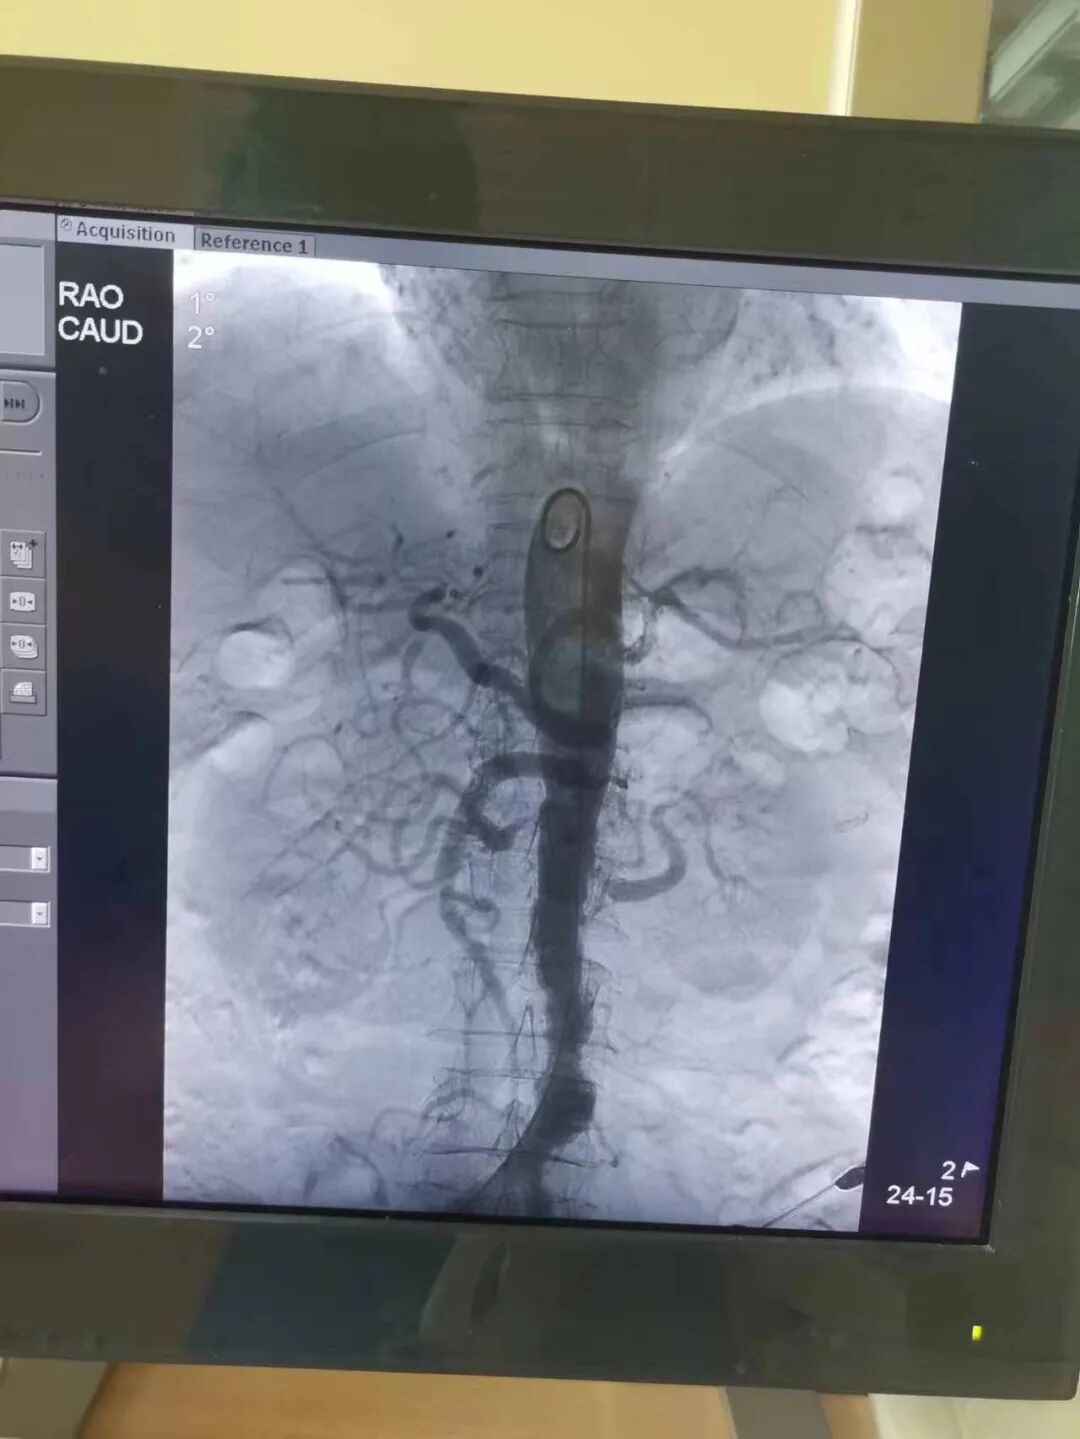

7月13日,在郑州市中心医院神经介入科专家王海波教授,介入团队副主任医师张晓平,主治医师韩旭超、邱帅兵等共同为患者行肾动脉球囊扩张成形及左肾动脉支架植入术。经过股动脉穿刺、肾动脉造影、狭窄处球囊扩张、支架植入、压迫包扎几个步骤之后,手术顺利结束。术后血压下降,头晕头痛、视物模糊等症状都得到有效改善,大大提高了生活质量。目前患者已康复出院。

神经内科一病区主任杨正伟介绍,“这个手术就像拓宽、疏通狭窄的河道一样,医生通过穿刺大腿根部的股动脉,将一个压缩得很小的球囊送到肾动脉狭窄处进行扩张,然后放血管支架,以撑开肾动脉。”